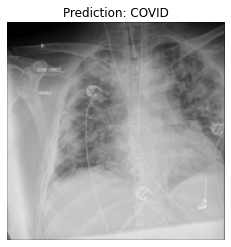

Currently, there is an urgent need for efficient tools to assess the diagnosis of COVID-19 patients. In this project, we propose a constructive solution for detecting and labeling infected tissues on CT lung images of such patients. To cut down false positives our model is trained on 4 types of lung CT images : COVID, Viral Pneumonia, Lung Opacity and normal images to get the best possible results with highest accuracy.

We built it using Tensorflow 2.x using Python. We have developed a Convolutional Neural Network model with an average accuracy of more than 85%.

We are proud that among the top 5 models, one of our models achieved 88.8% accuracy with very low loss.